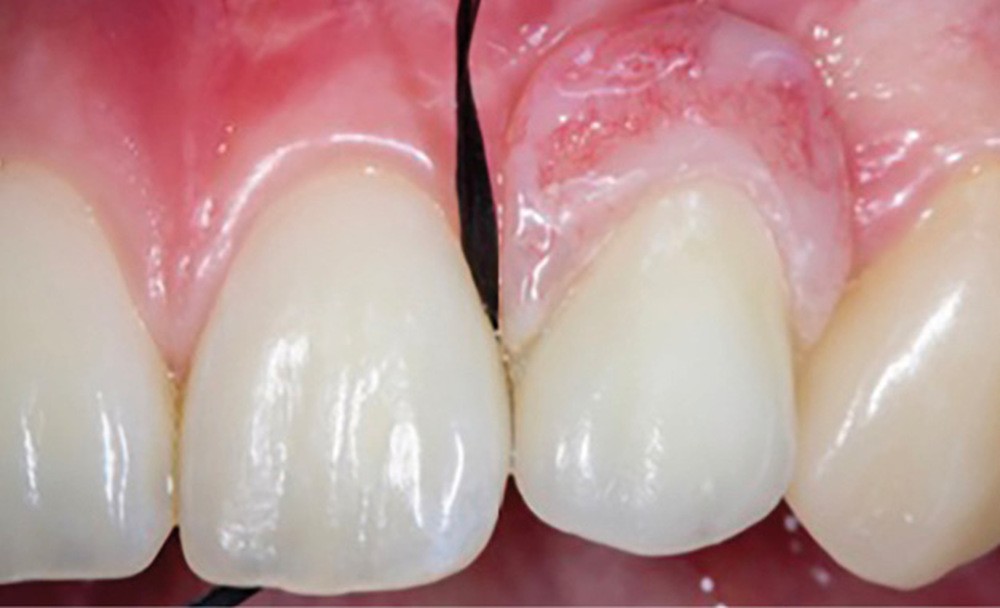

Enfin, la conception prothétique elle-même est à réfléchir, que ce soit en termes de profil d’émergence [18, 19] (pas de surcontour par exemple) (fig. 8) que d’accès à l’hygiène [20, 21] (fig. 9).